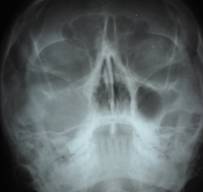

PRE OP OPG AND P A WATER'S VIEW SHOWS DISEASE